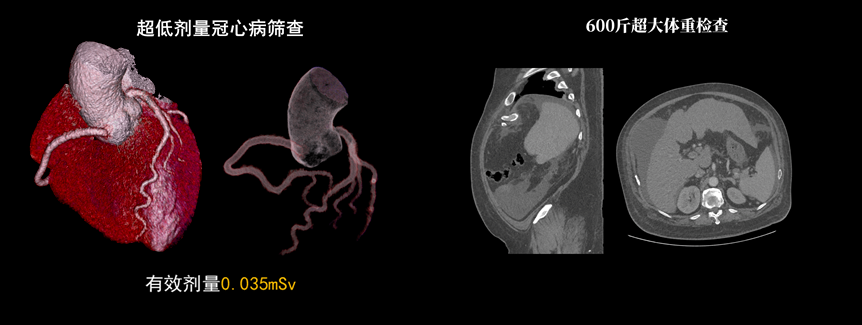

該設(shè)備除具備普通CT的功能外,還具備速度快、精度高、智能化、高效能、微劑量、大孔徑等優(yōu)勢(shì)。16厘米Z軸探測(cè)器、23毫秒時(shí)間分辨率,聯(lián)影天河640CT讓冠脈CTA檢查擁有“不選擇”的權(quán)利。搭載的一站式聯(lián)合掃描技術(shù),輔以便捷高效的后處理功能,AI精準(zhǔn)血管分割,自動(dòng)預(yù)處理加載,逐支血管觀察,全時(shí)提效,可實(shí)現(xiàn)一次注射造影劑獲取多部位CTA、CTP和4D動(dòng)態(tài)圖像,不僅可以助力腦卒中解決方案,還可助力腦血管畸形、腦動(dòng)脈瘤等其他腦血管病的結(jié)構(gòu)和功能評(píng)估。

液態(tài)金屬軸承球管,陽(yáng)極直冷技術(shù),提供30MHU球管熱容量,可高通量連續(xù)掃描。AI劑量調(diào)制、迭代重建等復(fù)合劑量控制方案,為體檢患者提供優(yōu)化劑量掃查。82cm大孔徑,讓大體型患者檢查更加舒適。

天河640CT的寬體探測(cè)器單圈掃描即可覆蓋全心臟,搭配快速機(jī)架轉(zhuǎn)速和獨(dú)家AI冠脈追焦技術(shù),可實(shí)現(xiàn)單心動(dòng)周期內(nèi)無限心率、無限心律的冠脈成像,對(duì)于嚴(yán)重心律不齊、房顫、房撲,超高心率等情況,天河640CT都能在單心動(dòng)周期內(nèi)獲得優(yōu)質(zhì)圖像。